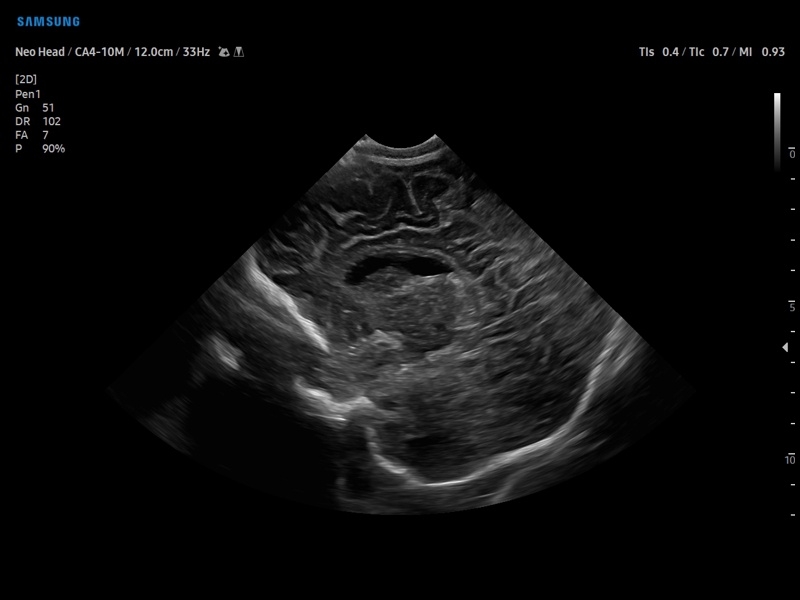

• Модуль5D CNS– программа автоматического построения основных срезов головного мозга плода в режиме объемного сканирования.